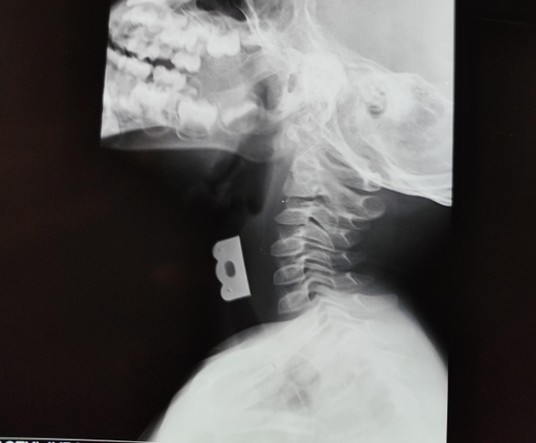

The child was stridulous on examination with nasal flaring, intercostal and subcostal recessions. He was afebrile, not pale, anicteric, not cyanosed, and not dehydrated. He was tachypneic with respiratory rate of 52 cycles/minute, oxygen saturation was 99% in room air, and other vital signs were within normal limits. A soft tissue X-ray of the neck and chest revealed a radio opaque object in the airway at the level of C4–C6 which is the region of the larynx as shown in Figures 1 and 2. A diagnosis of laryngeal foreign body was made.

Figure 2. Soft tissue X-ray of the neck revealing a radio opaque object in the airway (Lateral view).